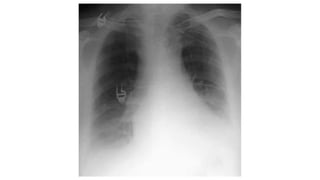

PREVIOUS CXR • PreviousCXRS your best friend. You see a real or possible abnormality on the CXR. • Was it there before? Has it got larger or smaller? Is it unchanged? • A previous CXR will often highlight an important but subtle change. • On the other hand it will frequently provide reassurance that all is well.